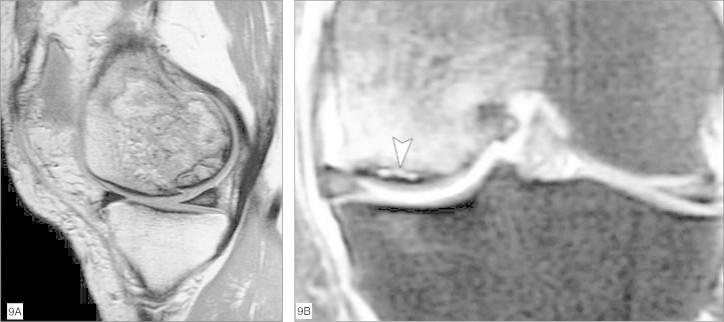

Through the ability of magnetic resonance imaging (MRI) to characterize soft tissue noninvasively, it has become an excellent method for evaluating cartilage. The development of new and faster methods allowed increased resolution and contrast in evaluating chondral structure, with greater diagnostic accuracy. In addition, physiological techniques for cartilage assessment that can detect early changes before the appearance of cracks and erosion have been developed. In this updating article, the various techniques for chondral assessment using knee MRI will be discussed and demonstrated.